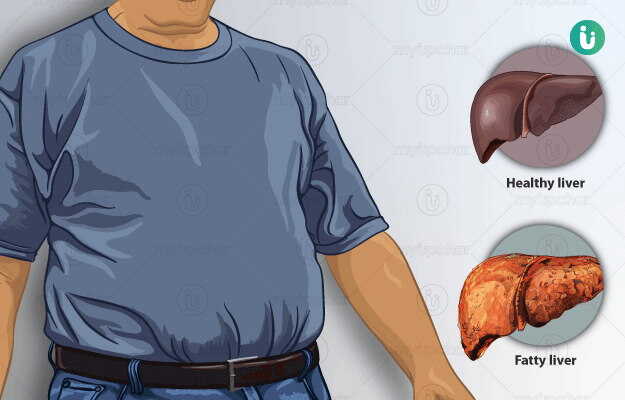

दूसरी ओर हमारी लाइफस्टाइल में खराबी की वजह से लिवर भी खराब हो सकता है और इससे जुड़ी बीमारियां हो सकती हैं, जिसमें से फैटी लिवर सबसे आम समस्या है।

बता दें फैटी लिवर तब होता है, जब लिवर में एक्सट्रा फैट इकट्ठा हो जाता है, इसके कारण इससे जुड़ी समस्याएं होने लगती हैं। ऐसे में इसके प्रति जागरूक होना बेहद जरुरी है, आइये जानते है इससे जुड़े कुछ फैक्ट्स (World Liver Day 2024) के बारे में –